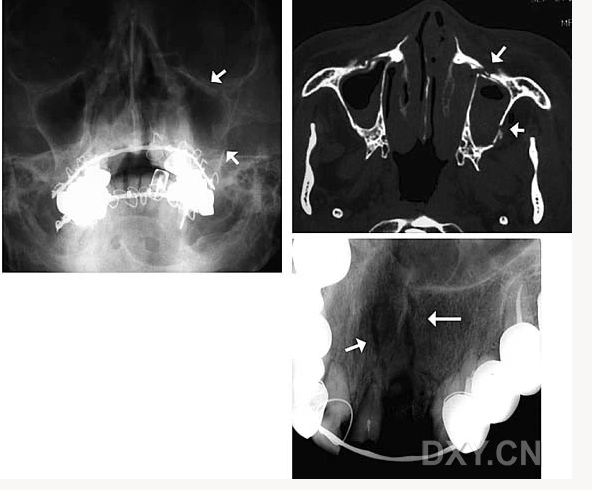

頜骨骨折

牙源性鈣化囊腫

牙瘤!

牙源性鈣化囊腫    牙瘤!

鼻腭囊腫